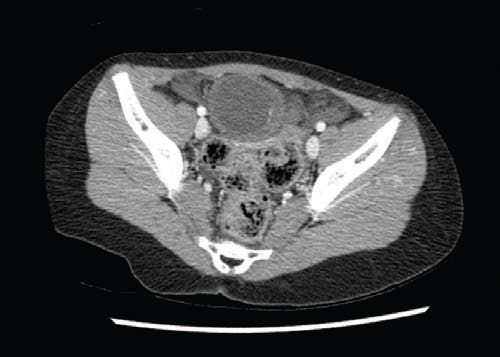

Alan Lucerna, DO; James Espinosa, MD; Jamey Hourigan, DO

A 7-year-old girl presented to the emergency department for evaluation of right lower quadrant abdominal pain.